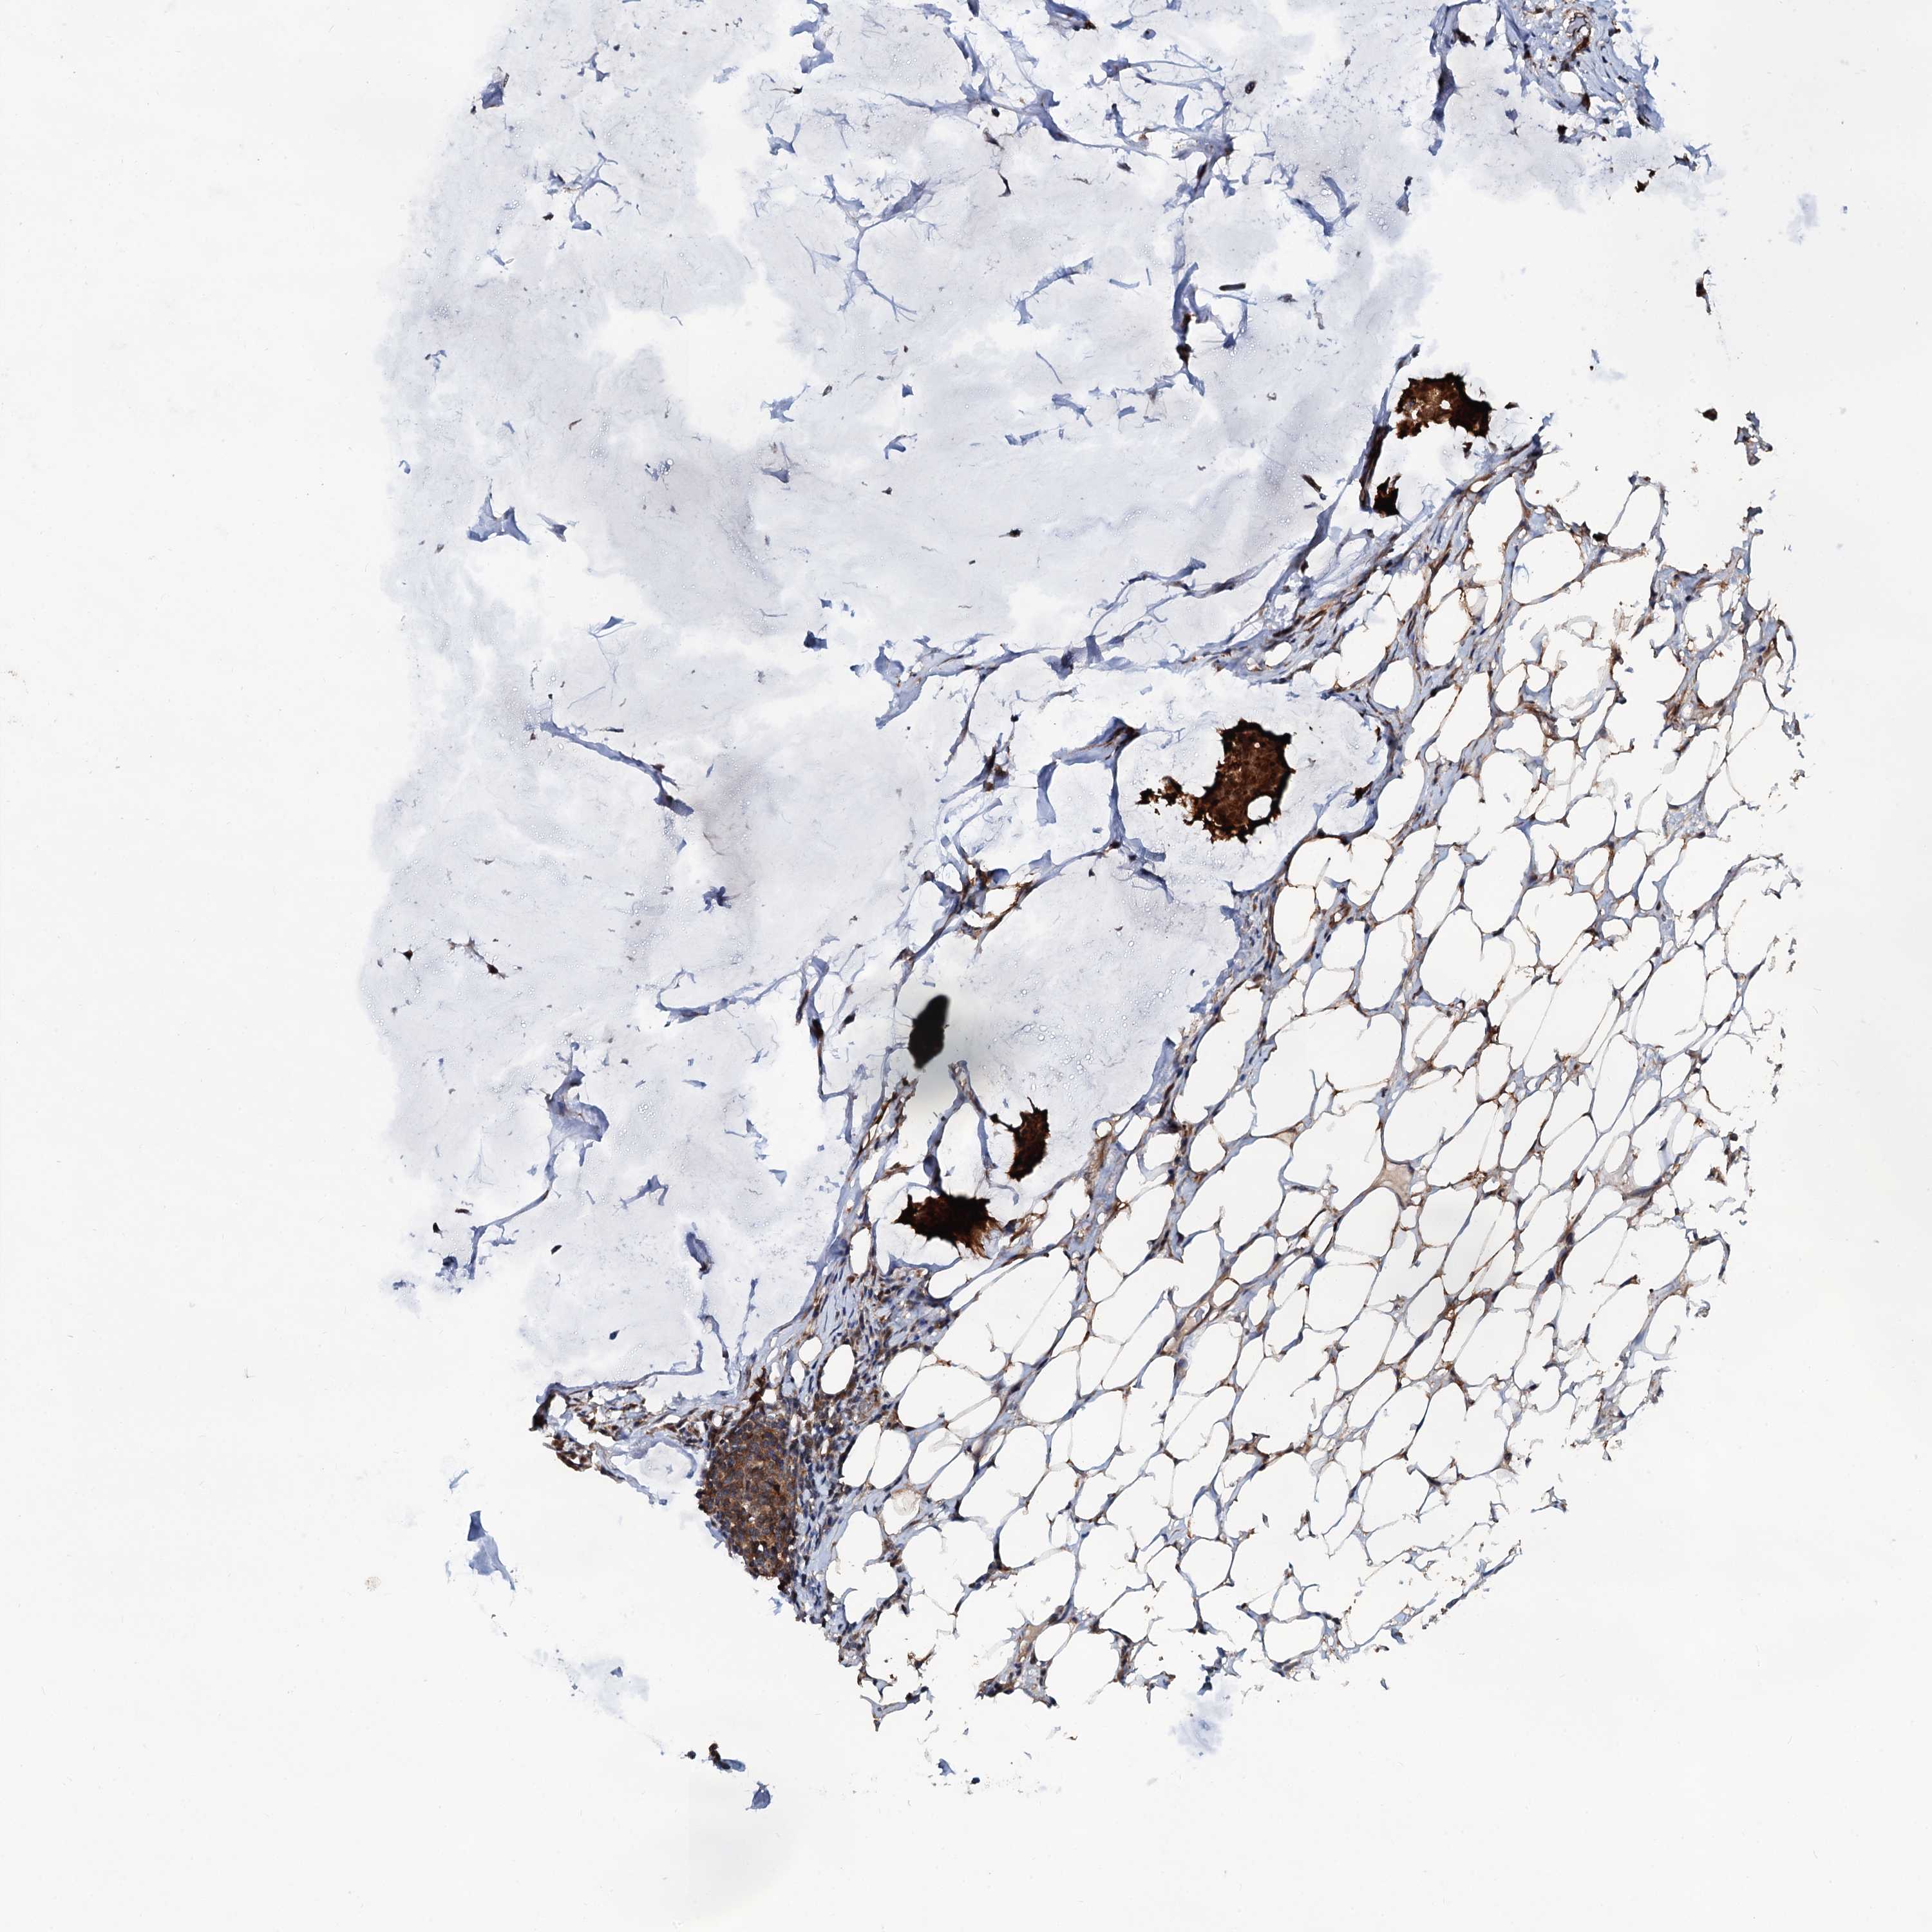

CANCER BREAST CANCER Show tissue menu

BRCA TCGA BRCA VALIDATION PROTEIN EXPRESSION